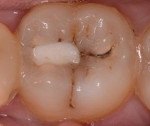

Внешние признаки включают пигментацию эмали около края печати, часто в форме края. Печать также может изменить цвет. Зуб становится сероватым, через эмаль просвечивает измененный дентин. На резцах эти изменения замечены раньше, чем на молярах. Иногда наблюдаются трещины и сколы зубной эмали и пломб. С серьезными дефектами подвижность печати может быть обнаружена; Если кариес развивается в течение длительного времени, а полость увеличена, пломба может выпасть. Бактериальный налет накапливается в трещинах, что приводит к неприятному запаху изо рта.